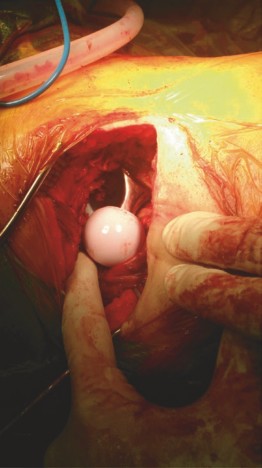

Neck Osteotomy and Head Removal

With the capsule open, a blunt retractor is placed superiorly over the femoral neck, and another is placed inferiorly to protect the circumflex vessels. The femoral neck osteotomy is performed in situ based on preoperative templating. A double cut (removing a "napkin ring" of bone) can be performed if the space is tight, facilitating easier removal of the femoral head. A corkscrew is inserted into the femoral head, and it is extracted utilizing a combination of traction and rotation.